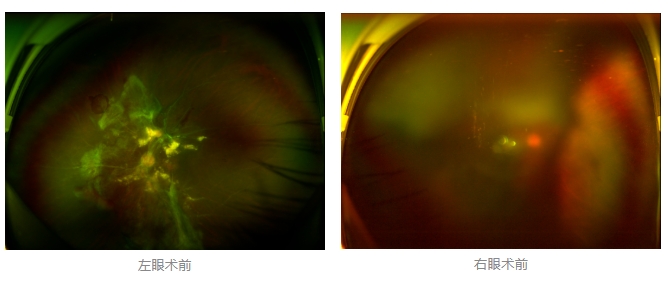

經(jīng)廈門眼科中心眼底病專科行政主任王曉波檢查后,確診其雙眼糖尿病視網(wǎng)膜病變VI期,伴發(fā)雙眼視網(wǎng)膜脫離和黃斑水腫,且右眼視網(wǎng)膜上增殖膜叢生,若再不盡快進行治療,恐有失明風險。

面對陳先生的復雜病情,王曉波主任采用玻璃體切割術聯(lián)合膜切除術等方式,精細剝離牽拉視網(wǎng)膜的增殖膜,復位脫離的視網(wǎng)膜,同時進行玻璃體腔注藥促進黃斑水腫吸收。

經(jīng)過規(guī)范化治療,術后2個月復查時陳先生的視力已有明顯改善,矯正視力從眼前指數(shù)提升至0.3,成功擺脫“失明危機”。但王曉波主任強調(diào):“這只是階段性勝利,后續(xù)治療不能松懈。”